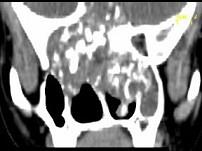

问题 男,26岁,进行性鼻腔阻塞、流涕来院就诊,近两年持续性头痛、头晕.如图所示筛窦区占位灶应诊断为 ( )

选项 A、骨结核伴左上颌窦炎 B、骨纤维异常增殖症伴左上颌窦炎 C、软骨瘤伴左上颌窦炎 D、骨化性纤维瘤伴左上颌窦炎 E、脊索瘤伴左上颌窦炎

答案 C